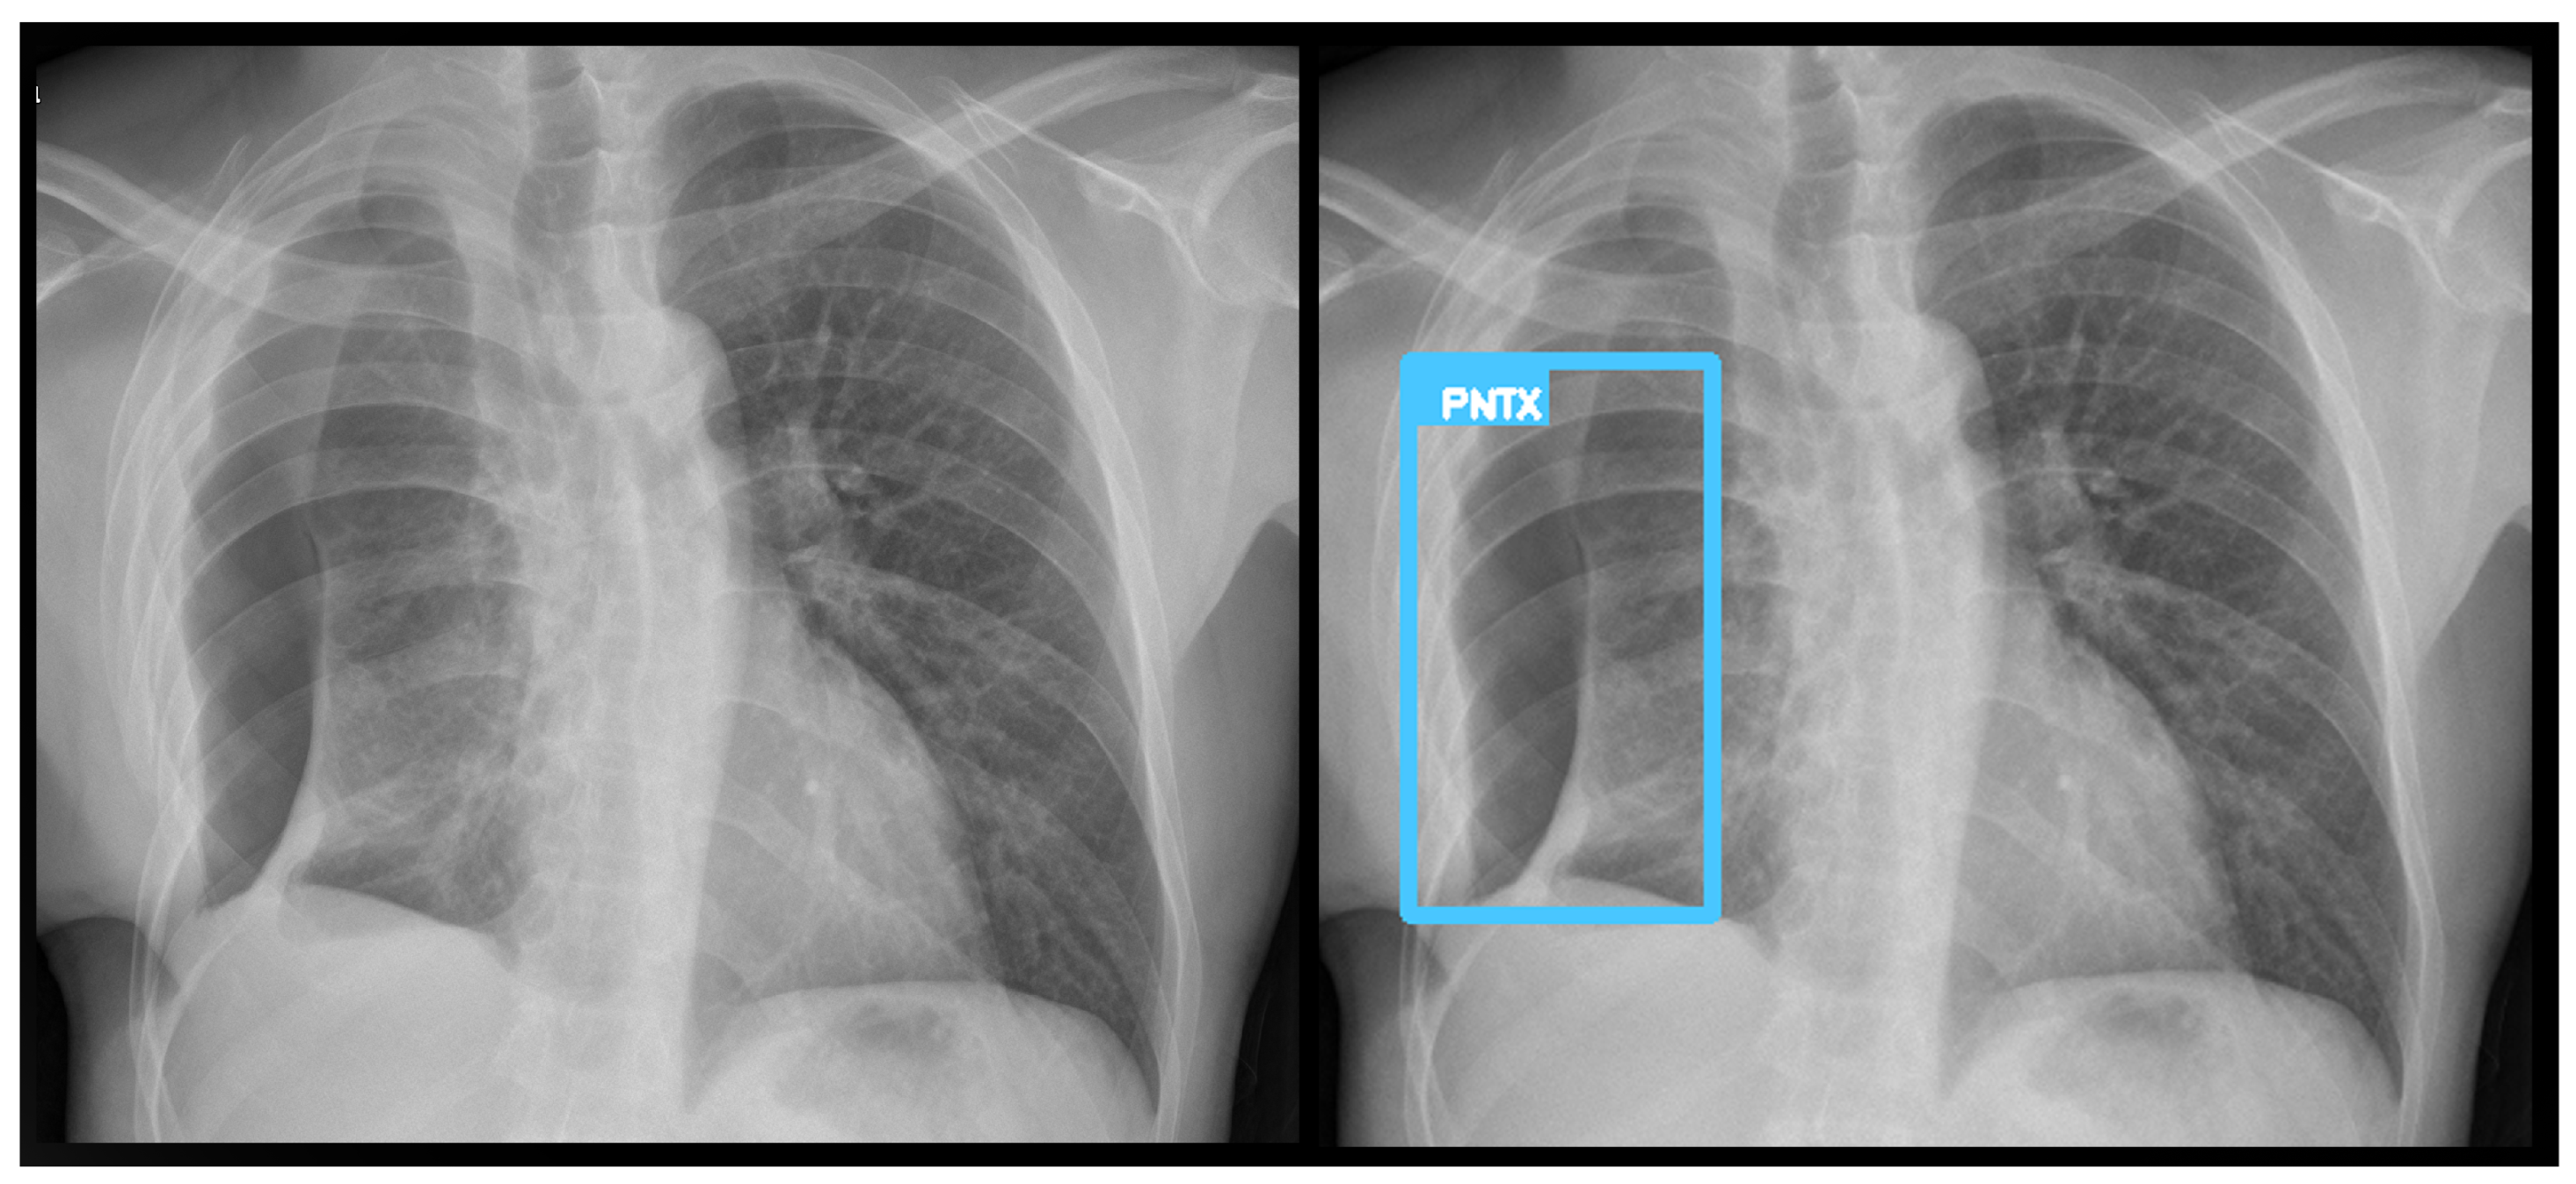

Figure 4. A true positive example of a nodule/mass (left) and its bounding box generated image (right). In this case, the report indicated opacity; however, the algorithm classified as a mass.

3.3. Error Analysis

An analysis of the algorithm’s false negatives revealed a nuanced performance profile, where a specific miss did not always equate to a complete system failure. Across the board, a substantial number of cases with a false negative for a particular pathology were nevertheless correctly identified as abnormal by the general “yes-finding” classifier or had other co-occurring true positive pathologies. For example, out of 38 false negatives for opacity, the algorithm correctly identified the exam as abnormal in 25 cases. In many instances of a missed finding, the algorithm successfully detected other pathologies within the same study. Misclassification was another notable source of error, where an existing pathology was detected but incorrectly labeled, such as opacities being predicted as masses or nodules (Figure 4). Radiologist review of these false-negative cases frequently noted findings that were “subtle,” “small,” “doubtful,” “seen on lateral image only,” or “non-specific.” In other cases, the algorithm correctly identified a more critical finding, like a large pleural effusion, while missing a secondary, less significant pathology (Figure 3). Figure 9, Figure 10 and Figure 11 illustrate false negative cases for opacity, pneumothorax, and nodule, respectively. This highlights the inherent limitations and inevitable failures of this kind of system.